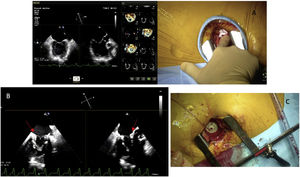

Las intervenciones se realizaron bajo anestesia general mediante una minitoracotomía anterolateral izquierda de unos 4cm en el 5.° espacio intercostal. Todo el procedimiento es monitorizado mediante ecocardiografía transesofágica y fluoroscopia. El implante se realiza sin circulación extracorpórea. La elección del punto de acceso apical se define preoperatoriamente con las pruebas de imagen, y se confirma en quirófano por el «Finger test». La válvula se implanta a través del ápex con introductor de 34Fr (fig. 2).